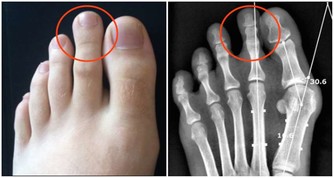

腳趾疼痛如果你經常在沒有明顯原因的情況下腳趾疼痛,並且在休息時注意到腿部寒冷或麻木,這也是主髂動脈閉塞性疾病的一個跡象。